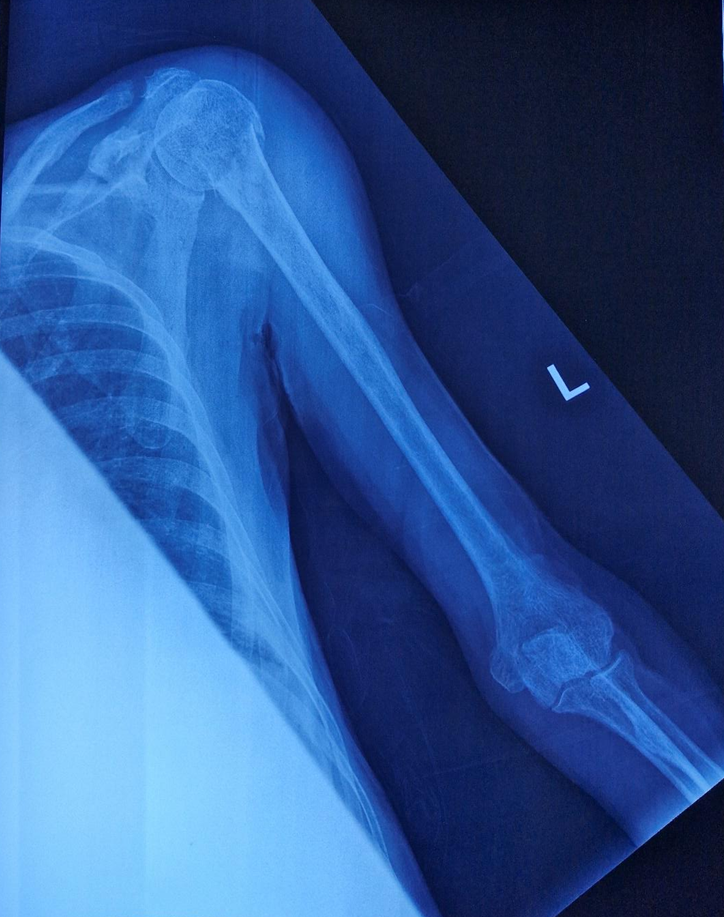

Imaging: X-ray revealed a left neck of humerus fracture.

1) left neck of humerus fracture